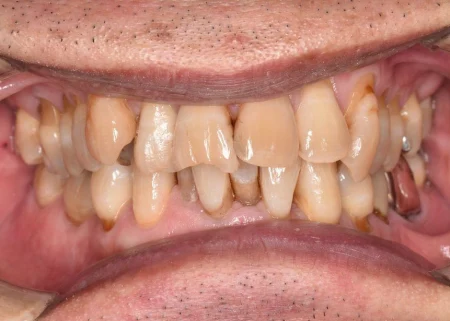

治療後

| 術後の経過・現在の様子 | 着色がきれいに取れて歯本来の自然な白さになり、歯肉も引き締まって歯周病が改善されました。 患者様も「歯がきれいになってうれしい。舌触りも変わった」と喜ばれていました。 現在は、最初にご相談いただいた詰め物のやり直しを進め、より美しく健康な状態となってきています。 |